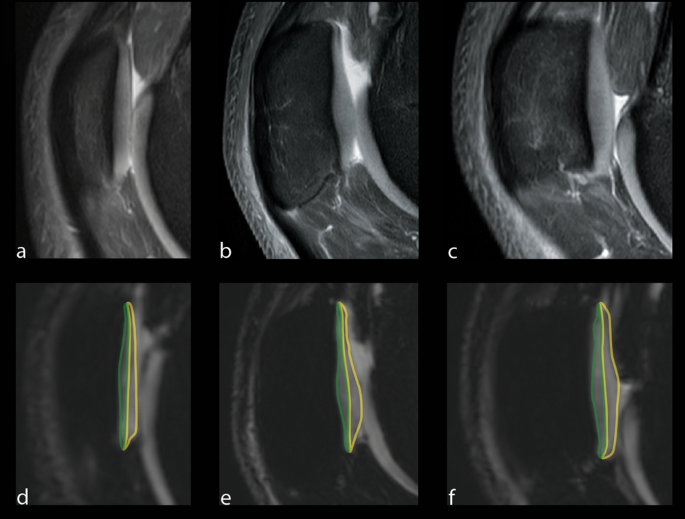

The patella was evenly divided into a lateral, central, and medial compartment for quantitative analysis49. The trochlea sulcus served as the anatomic landmark for the central compartment. The total numbers of slices covering the retropatellar cartilage were assessed both to the lateral and medial borders of the patella. Quantitative image analysis was performed on the two most central consecutive slices of each compartment. The articular cartilage of the patella was outlined without any subchondral bone and synovial fluid. A specific bone–cartilage threshold was set for each participant to automatically remove possible included cortical bone pixels within the ROIs. Each compartment of the cartilage was evenly divided into two layers, representing superficial and deep layers (Fig. 5).

The predefined areas of the retropatellar cartilage for T2* measurements with the corresponding PD weighted images for morphological orientation (a–c). T2* measurements were performed on sagittal images in the deep (region of interest in green) and superficial (region of interest in yellow) layer of the retropatellar cartilage. Measurement were performed in the lateral (d), central (e) and the medial (f) compartment of the joint space.

In each compartment, ROI analysis was performed on the two most central consecutive slice images of each compartment, using a dedicated software application (ImageJ). The average of the T2* values of the consecutive images was defined as the T2* value of the ROI, as performed elsewhere49. The voxel count of the ROIs was documented (138.3 ± 18.81 voxels [minimum 113, maximum 186]) as well as the number of voxel layers in each cartilage layer (mean 6; range 5–7).